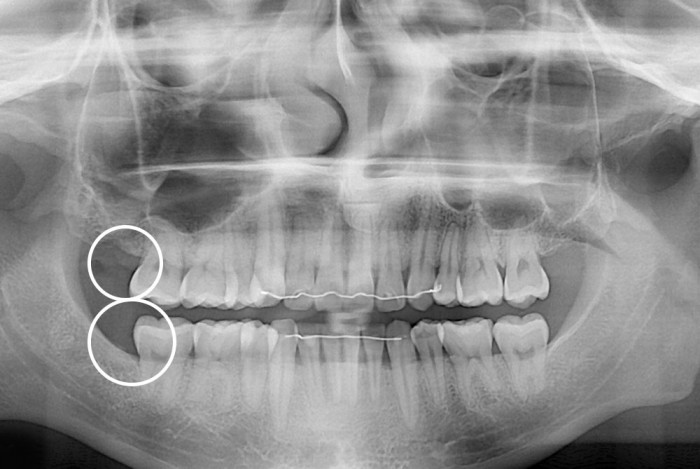

[사랑니] 매복 사랑니 발치

치료전 : 2020-01-29